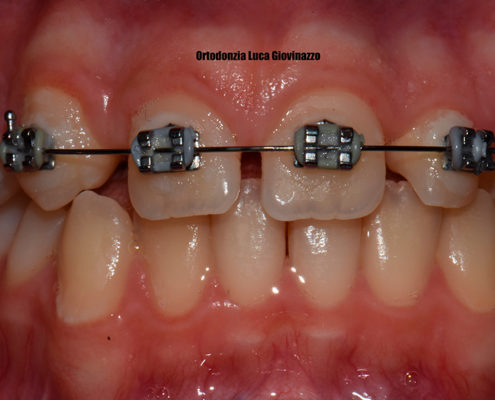

La prima visita ci mette nella condizione di valutare lo stato di salute e igiene del paziente, successivamente i modelli studio e le radiografie completano lo studio. La Ortopantomografia permette di evidenziare la genesi degli elementi dentari e valutare la reale presenza numerica di tutti i denti. La telecranio latero laterale ci permette di mettere in relazione il profilo del volto con le strutture dento/scheletriche, gestire dei piani e angoli che daranno vita al piano di trattamento congiunto alla visita e alle richieste del paziente, sommandole spesso a quelle dei genitori.